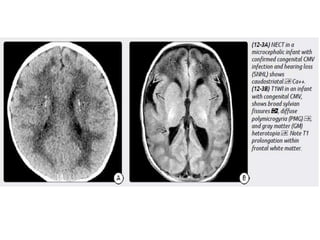

Congenital (Perinatal) HIV

Imaging

Atrophy, particularly in the frontal lobes.

Bilaterally symmetric basal ganglia calcifications.

Ectasia and fusiform enlargement of intracranial arteries.

Strokes with foci of restricted diffusion and subarachnoid hemorrhage

may occur as complications of the underlying vasculopathy.

Congenital (Perinatal) HIV Imaging Atrophy,particularly in the frontal lobes. Bilaterally symmetric basal ganglia calcifications. Ectasia and fusiform enlargement of intracranial arteries. Strokes with foci of restricted diffusion and subarachnoid hemorrhage may occur as complications of the underlying vasculopathy.